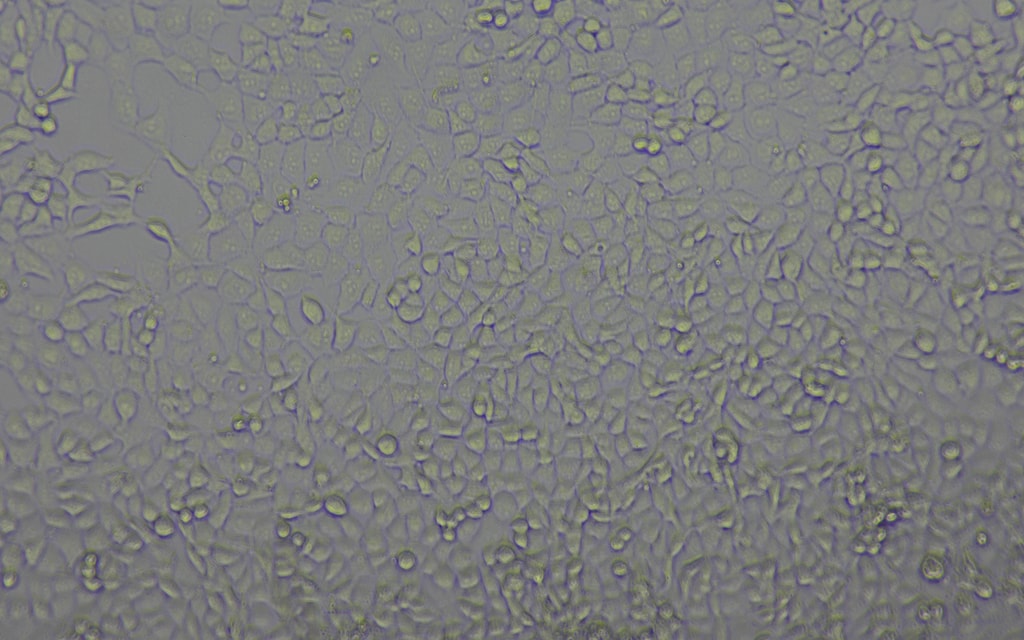

Our science is validated sufficiently, and we have clinical proof that Leukocyte-Tells (SL-28) works. Here is IRL imagery to show it.

Donor derived leukocyte

(CD8+ T cells, CD15+)

Leukocyte-Tells

(SL-28)